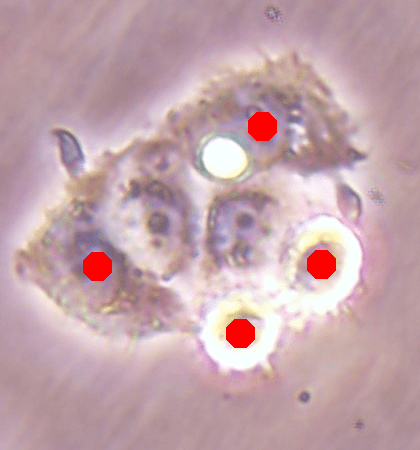

Before the advances in deep learning, the traditional approach for cell detection/segmentation is to employ low-level handcrafted features, reflecting color, edge, and shape characteristics of cells. This approach has given promising results when the features are defined properly, as a good representation of the visual cell characteristics. On the other hand, these characteristics may change from one cell type to another (see Fig. 1) and new features need to be defined to meet the cell characteristics of a new type. Additionally, when there exists heterogeneity in the visual characteristics of the same cell type, using a single model may not be sufficient to detect all cells of this type, particularly for cancer cells which are exploited more in high throughput screening.

![]() |

| (a) | (b) | (c) |

We test our DeepDistance model on three datasets, each of which consists of live cell images of a different cell line. They are the CAMA-1, MDA-MB-453, and MDA-MB-468 human breast cancer cell lines. The images in all datasets were acquired at magnification and pixel resolution. An example image from each dataset is shown in Fig. 1. As seen in this figure, cells might be visually different within and across different cell lines.